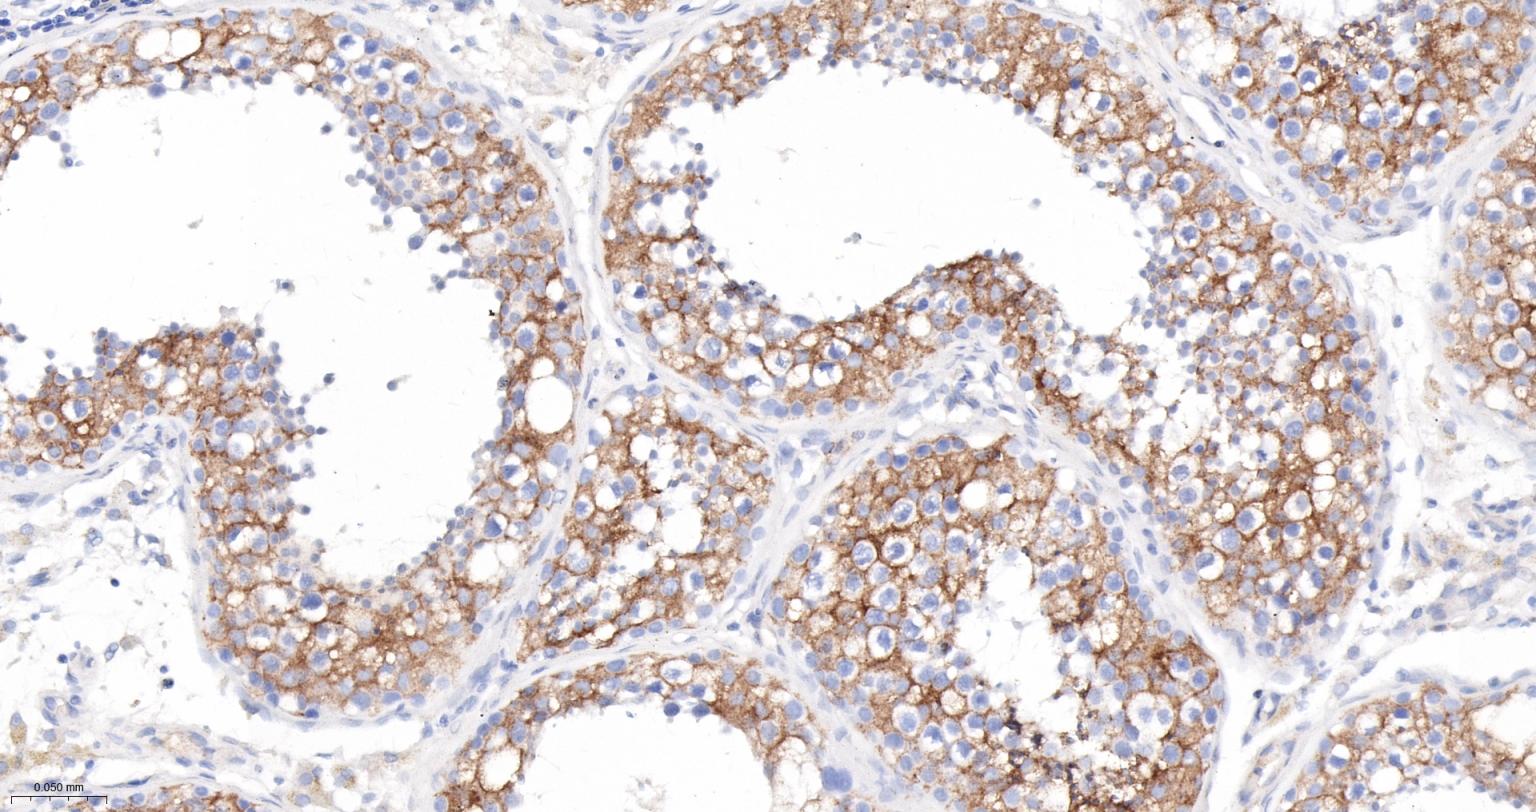

Paraformaldehyde-fixed, paraffin embedded Human Testicles; Antigen retrieval by boiling in sodium citrate buffer (pH6.0) for 15 min; The section was incubated with PRKAR2B Monoclonal Antibody, Unconjugated (bsm-61473R) at 1:200 overnight at 4°C, followed by conjugation to the bs-0295G-HRP and DAB (C-0010) staining.